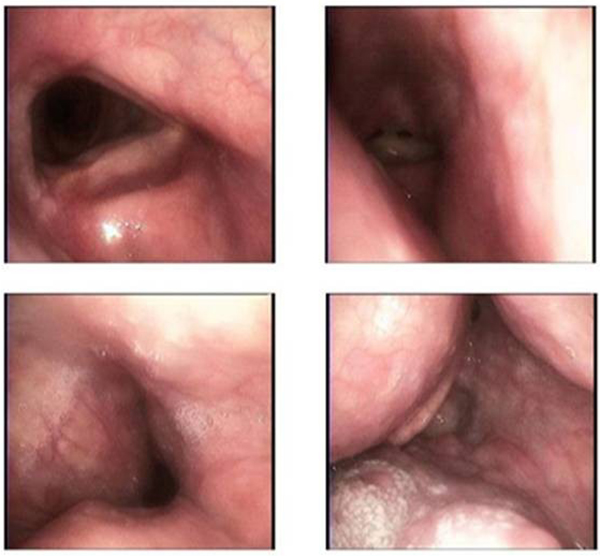

患者劉先今年60多歲,近2年來無明顯誘因出現(xiàn)咽部異物感,伴睡覺打鼾,偶有憋醒,外院CT示:咽后壁腫物。為求進(jìn)一步治療,收住徐醫(yī)附院;颊哂刑悄虿、高血壓病史。2月12日,患者電子鼻咽喉鏡檢查結(jié)果顯示,鼻咽部見光滑隆起,上起自軟腭水平的右側(cè)咽側(cè)壁,擠壓至喉腔狹窄,下段擠壓會(huì)議,右側(cè)會(huì)厭谷、杓會(huì)厭皺襞、梨狀窩及食管入口不可見,右側(cè)聲帶活動(dòng)受限。當(dāng)天的磁共振頸部平掃檢查結(jié)果顯示,口咽、喉咽右后壁示團(tuán)塊狀短T1信號(hào)影,T2壓脂呈低信號(hào),邊界尚清,大小約41mm*26mm*89mm,咽腔變窄?剖页醪皆\斷“咽旁間隙脂肪瘤”。

2月13日,麻醉科王光磊主任醫(yī)師和鄧倩主治醫(yī)師為患者實(shí)施全身麻醉,麻醉時(shí)見患者咽腔狹窄,聲門暴露困難,王光磊主任醫(yī)師立即更改為纖支鏡下經(jīng)鼻清醒插管,麻醉順利實(shí)施。手術(shù)由華夏副主任醫(yī)師主刀,張旭主任醫(yī)師、曹恒明副主任醫(yī)師指導(dǎo),臧云鵬主治醫(yī)師配合,為患者行口內(nèi)鏡下咽旁間隙腫瘤切除術(shù),術(shù)中使用開口器暴露口咽部,見咽后壁右側(cè)隆起,自鼻咽部延至?xí)䥇捤,在?nèi)鏡下操作,鉗夾隆起處粘膜,腫瘤正中等離子切開,暴露腫物實(shí)質(zhì)為脂肪樣新生物,鈍性分離后與等離子結(jié)合,延其與周圍肌肉間隙完整切除。手術(shù)僅持續(xù)50分鐘,術(shù)中出血量不到50ml。